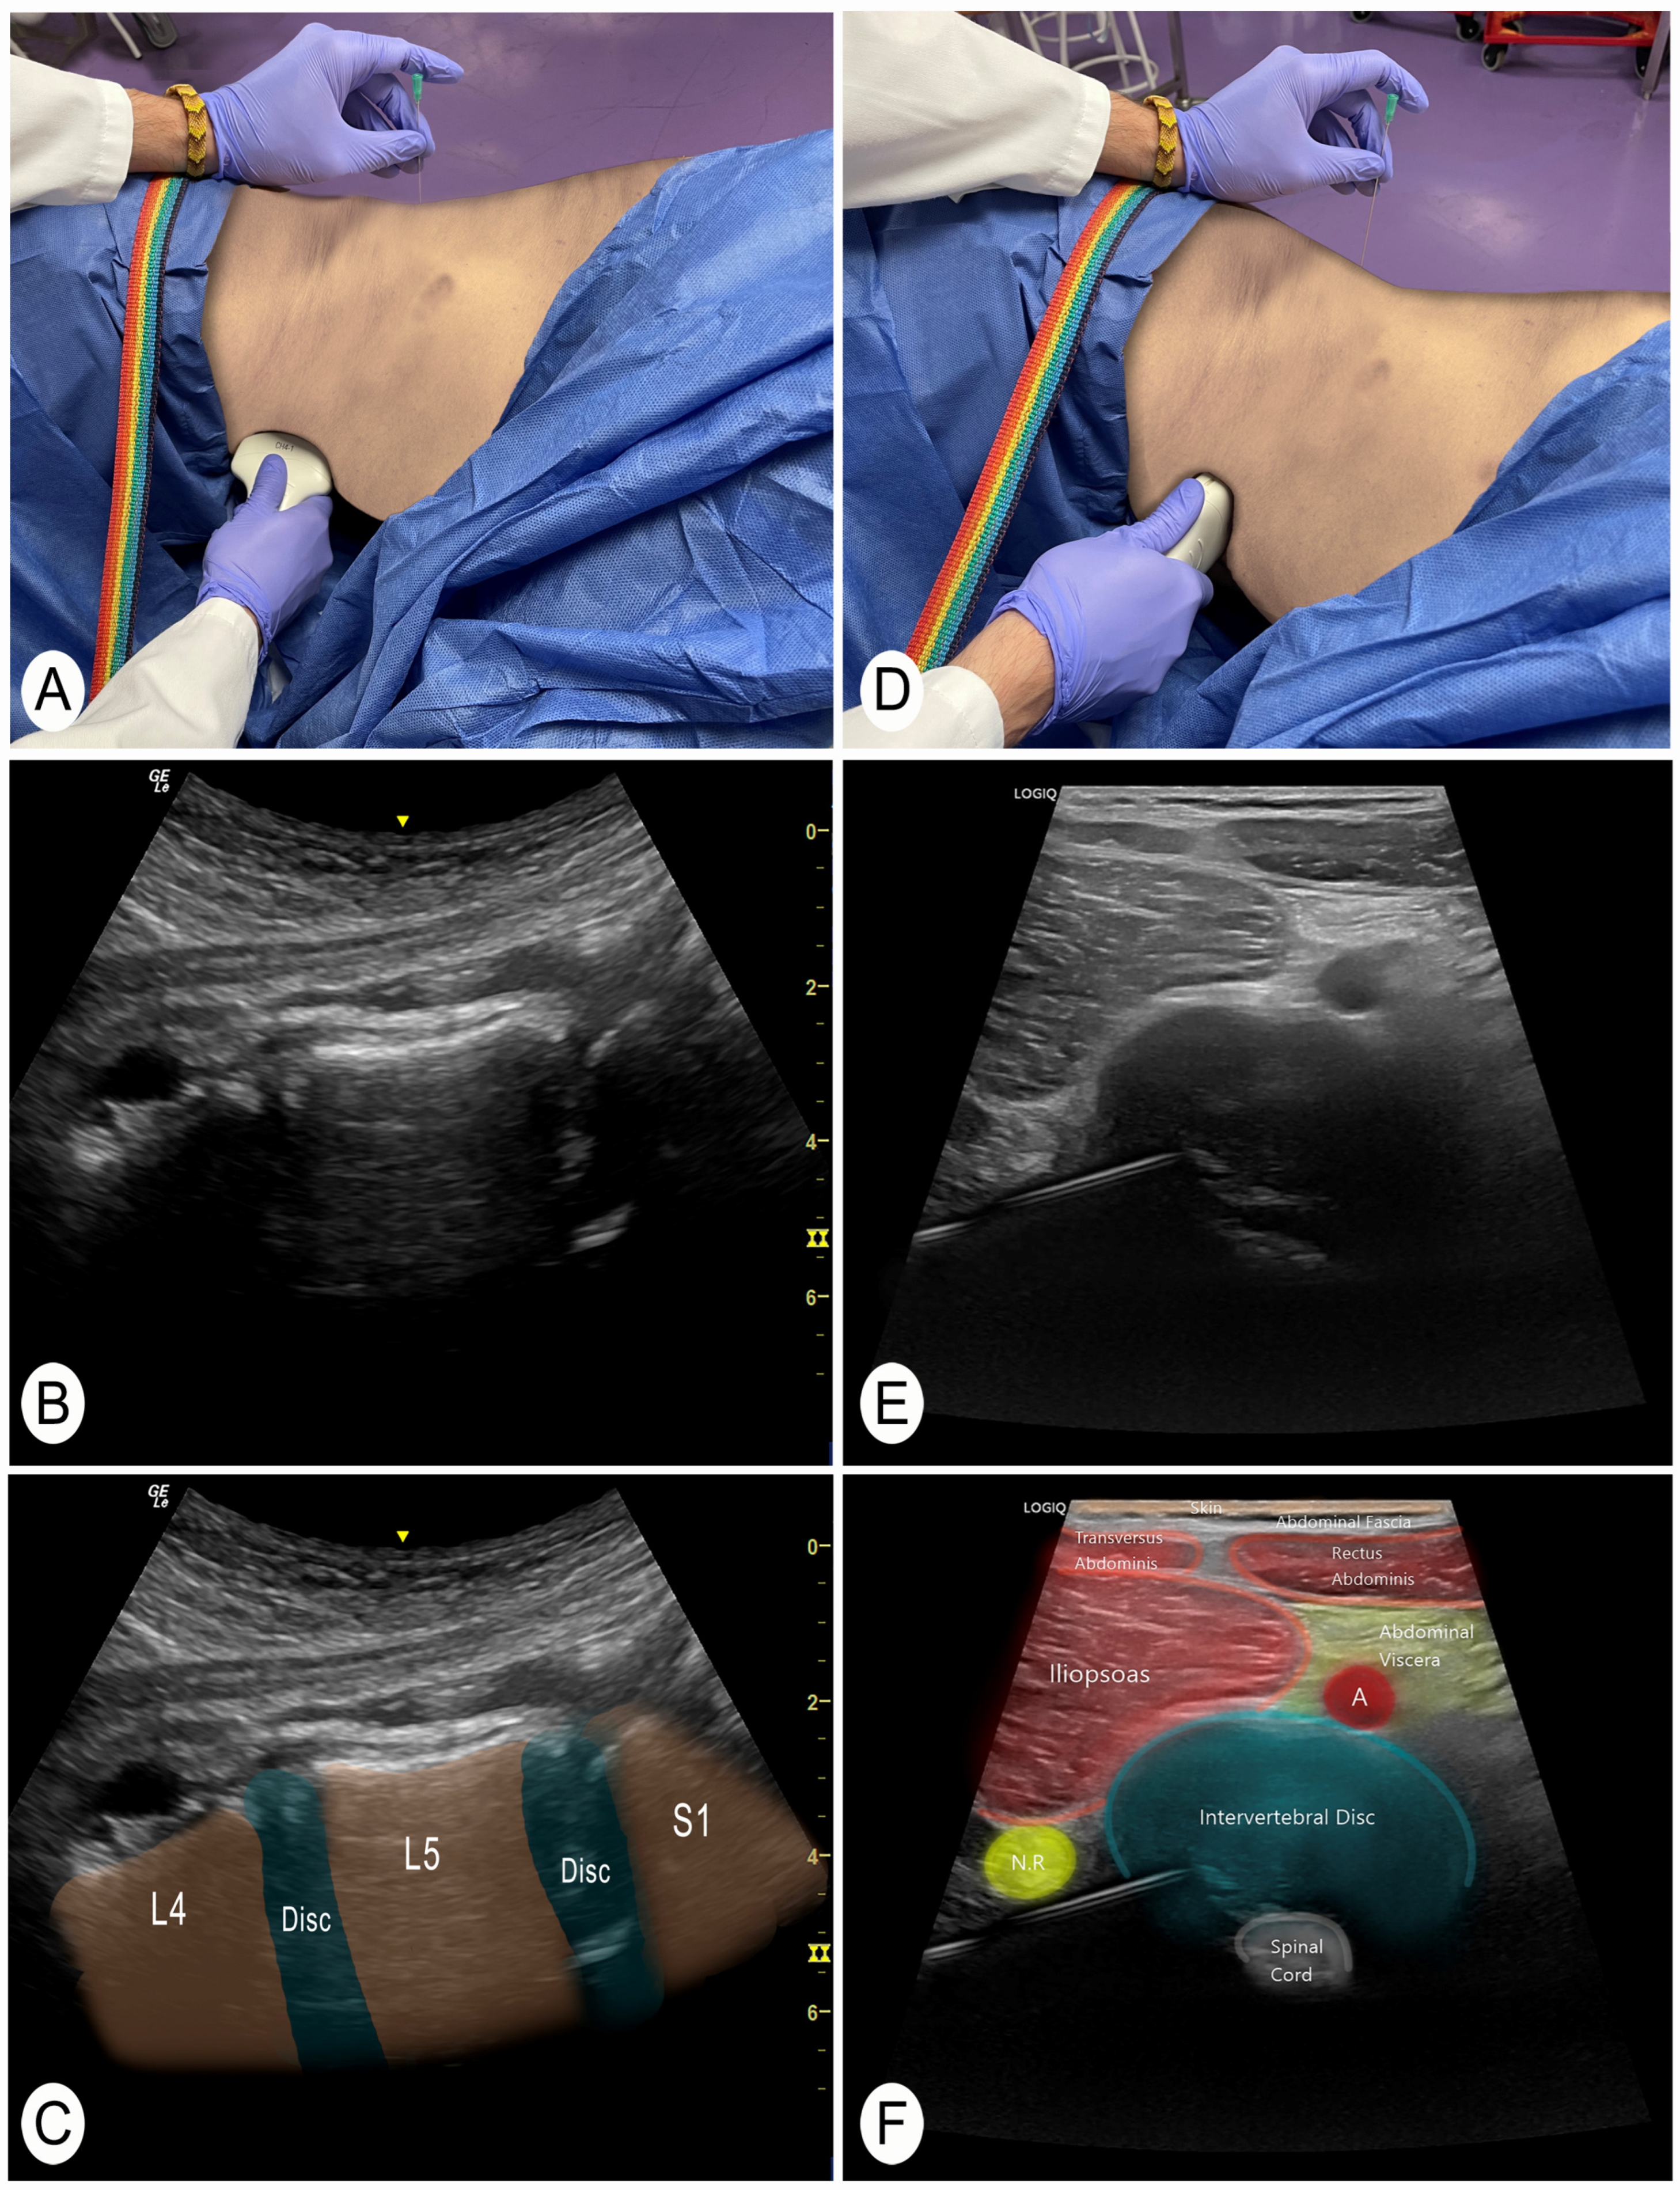

The same procedure was performed at each lumbar segment. When performing this technique on live subjects, it is advisable to use the power Doppler function to identify vascular structures and not to pass through them. Once this check has been performed, the needle is placed in the center of the transducer (in-plane). During needle insertion, the tip of the needle must always be visualized until contacting the posterolateral part of the intervertebral disc. The nerve root should also be visualized to avoid perforating it. When the needle is slightly introduced into the intervertebral disc, a fibrous texture can be felt that confirms this structure. The ultrasound image was then saved for further measurements. The transducer is then removed and placed in the patient’s abdomen (the needle remains inserted, only the transducer moves) (Figure 3A). The objective is to visualize the needle from the patient’s abdomen. To do this, the target segment is located again, but now from the patient’s abdomen. The process starts with a longitudinal cut of the spine to identify the vertebral levels (Figure 3A–C). When the segment where the needle is located is identified, a cross-section of that intervertebral disc is performed to visualize the needle in plane (Figure 3D–F). Finally, final adjustments are made to the needle to bring it to the target disc area. A second ultrasound image is then saved for further measurements.

Figure 3.

Anterior and slightly lateral view of the intervertebral disc. Abbreviations: N.R., nerve root; A, artery. L4, 4th lumbar vertebra; L5, 5th lumbar vertebra; S1, 1st sacral vertebra. (A) Position to locate the vertebral level with the transducer in a longitudinal slice of the vertebrae from the abdomen. (B) Ultrasound image of the longitudinal section of the lumbar levels from a ventral view. (C) Ultrasound image of the longitudinal section of the lumbar levels from a ventral view with the vertebral segments identified. (D) Position of the transducer in a cross-section of the intervertebral disc previously punctured. (E) Cross-sectional ultrasound image of the intervertebral disc from a ventral view where the previously inserted needle is located and adjusted. (F) Ultrasound cross-sectional identification of the structures.